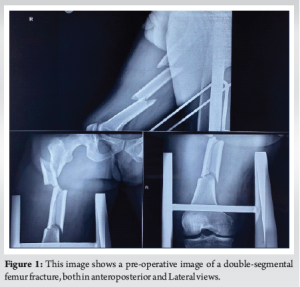

After being transferred from a rural community hospital following a traffic accident, a 35-year-old male patient arrived at our emergency department. There was no past medical history. Acute right limb pain and widespread thigh edema were discovered during the initial clinical evaluation; there were no skin lacerations, and there was clear deformity. There was no evidence of neurovascular dysfunction. Multiple femoral fractures at the subtrochanteric, diaphyseal, and supracondylar regions were visible on plain radiographs of the pelvis and right femur as shown in (Fig. 1). The proximal bone section was anterolaterally displaced due to an oblique subtrochanteric fracture. In addition, a transverse fracture with anteromedial displacement of a comminuted fragment was observed in the diaphyseal area. Finally, a transverse fracture in the supracondylar area with a flexed distal fragment. Vital signs were stable; hemoglobin (Hb) was 10.2 g/dL (normal 13.5–17.5), and the hematocrit (HCT) was 30.2% (normal 40–54%) at admission. Due to the patient’s HCT falling to 27.3% (Hb = 9.3 g/dL), a single packed red blood cell (RBC) transfusion was performed on the 2nd day of hospitalization. After written and informed consent and after clearance from anesthesia patient was planned for surgery.